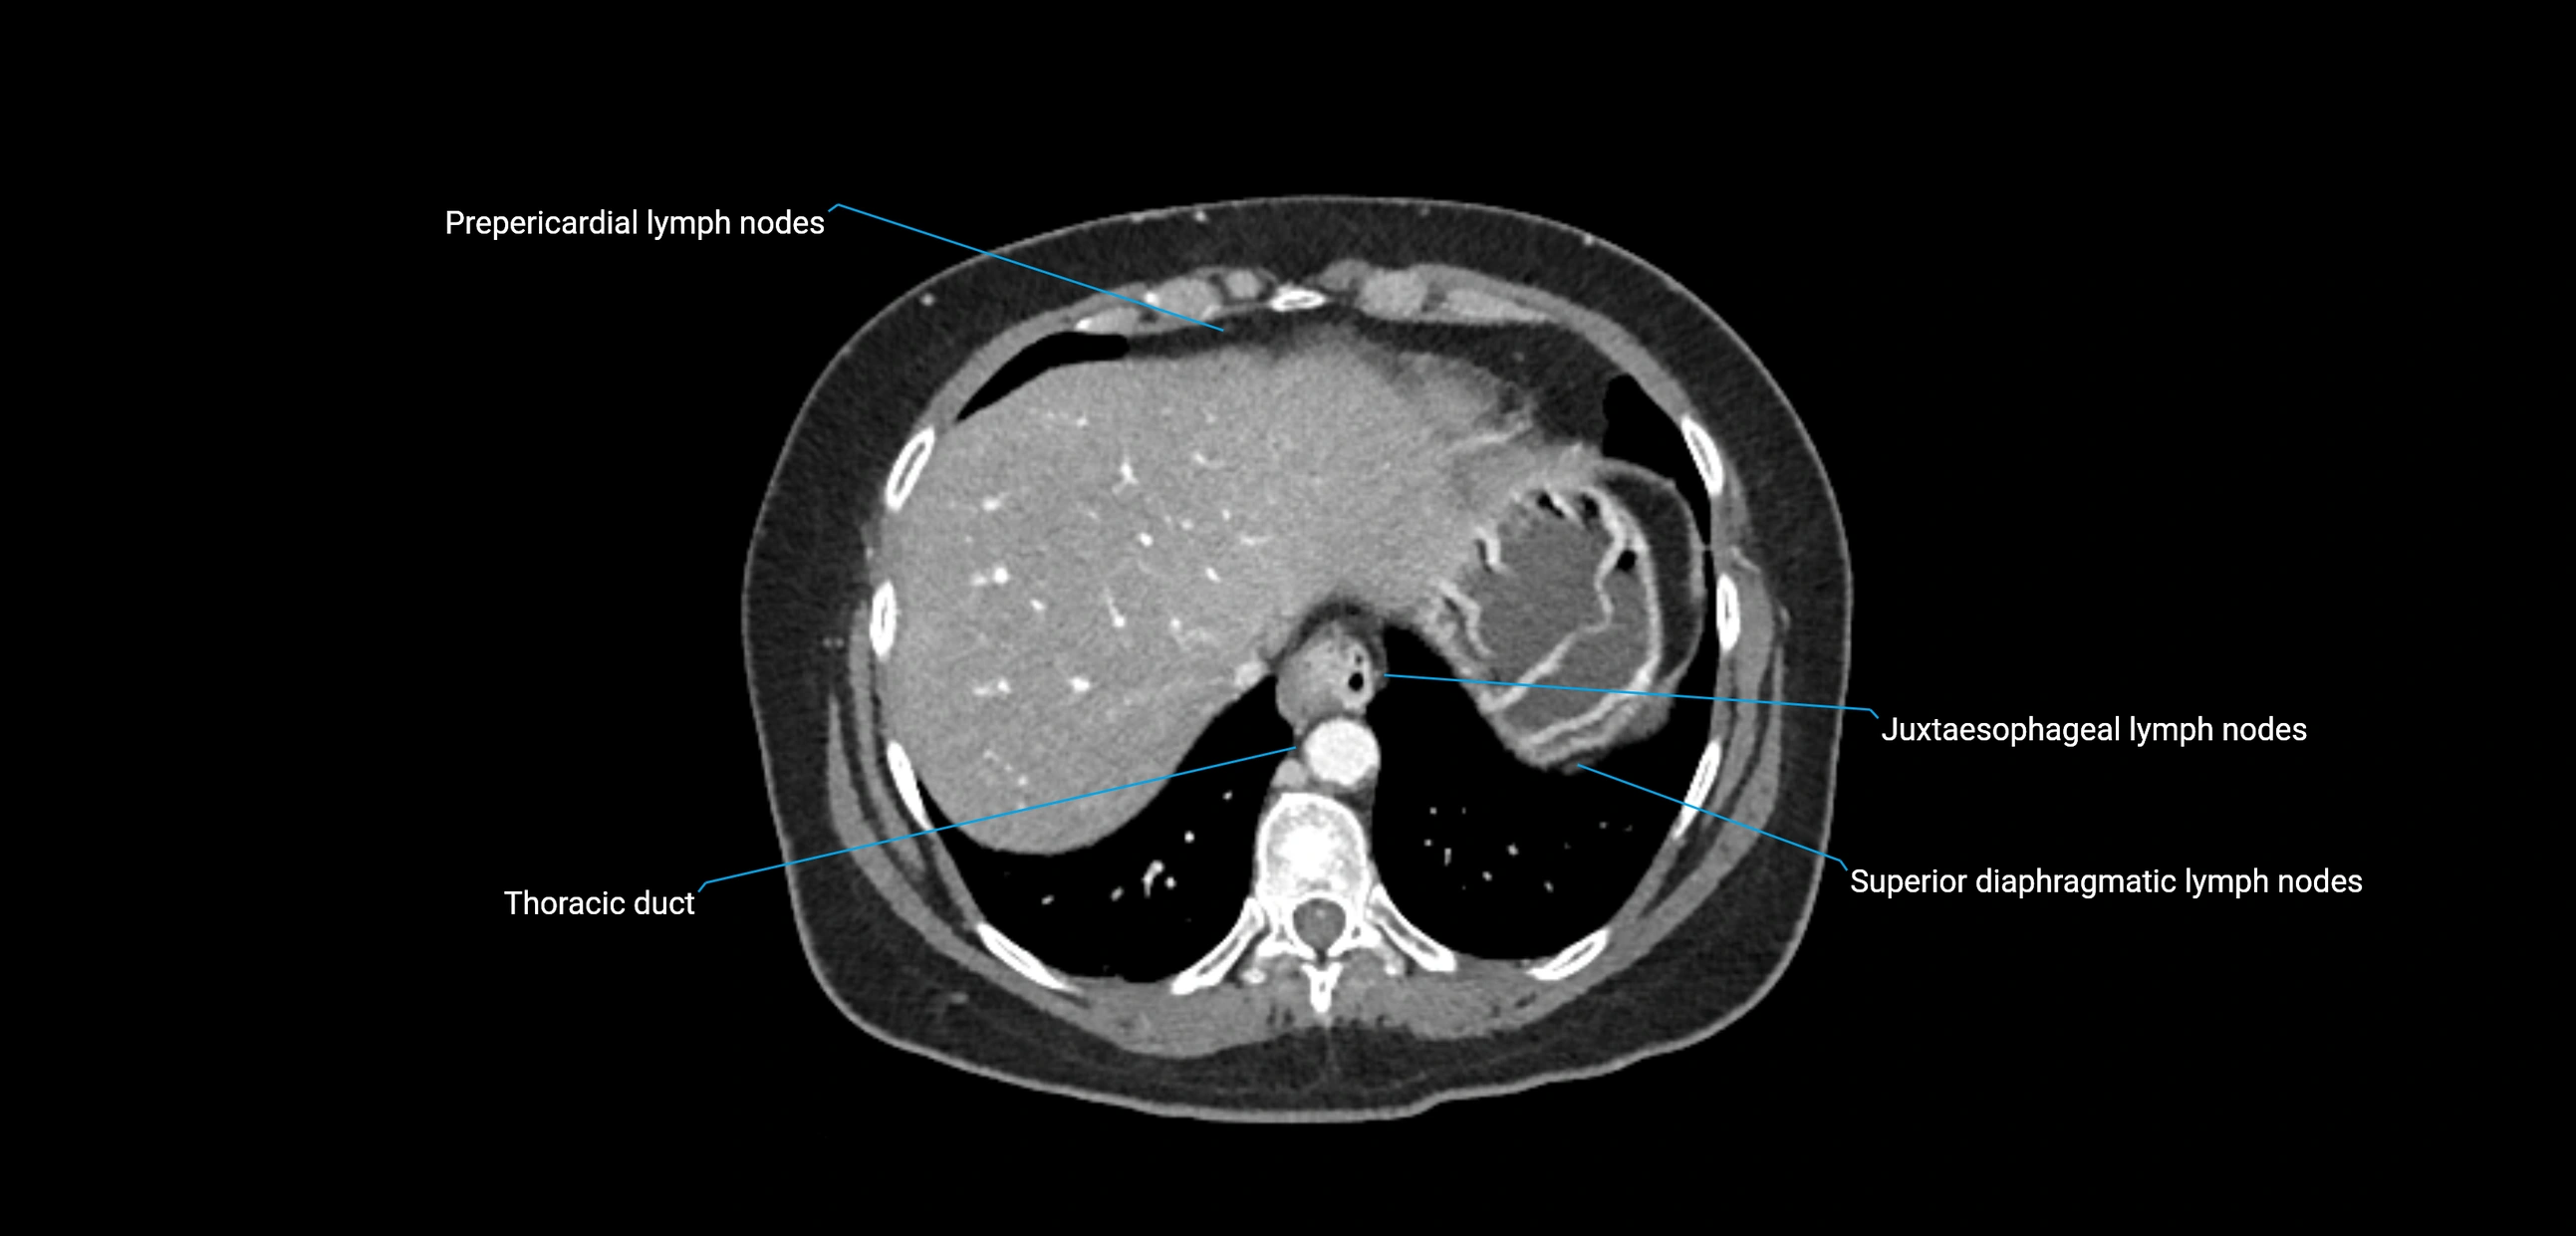

CT image

image